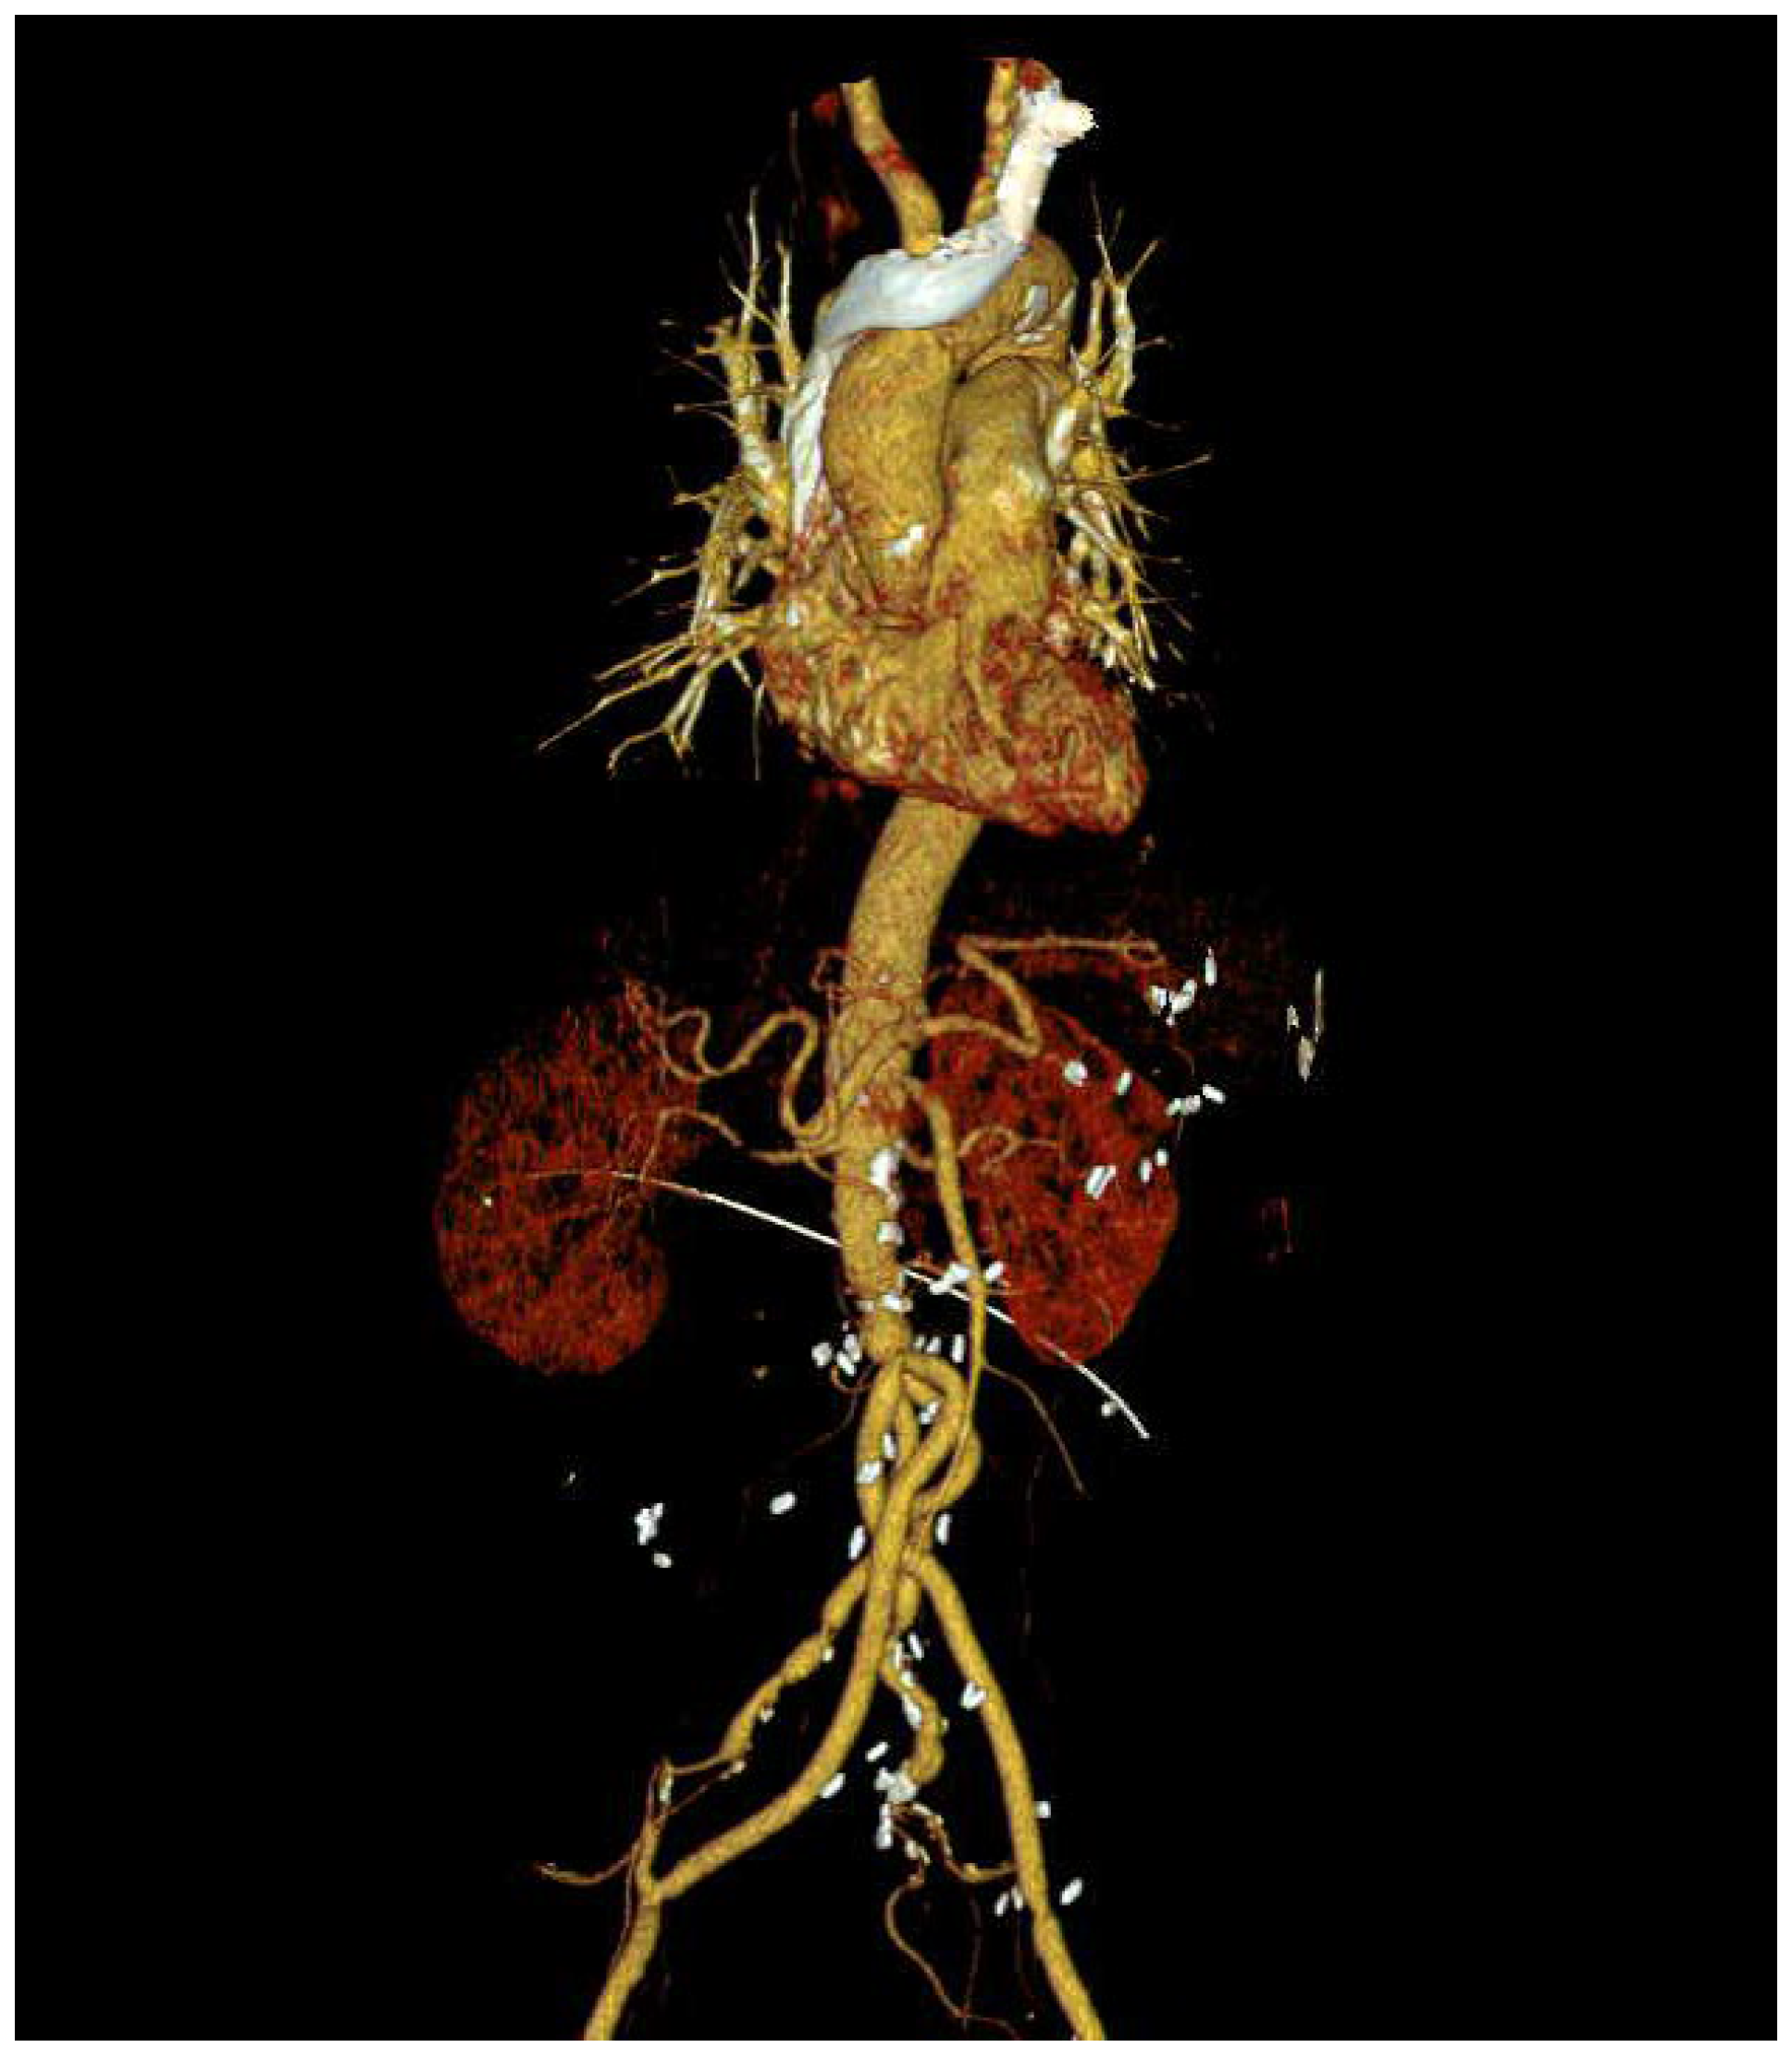

Five months later, the patient was readmitted to the emergency room for a recurrence of a fever of unknown origin. Leukocytosis was observed, but other laboratory examinations revealed no specific findings. To evaluate the focus of the fever, chest and abdominal CT scans were performed, as shown in Figure 3. The findings revealed a contained rupture of the mycotic abdominal aortic aneurysm (AAA). The patient underwent emergency AAA repair using an antibiotic-soaked graft. No complications were observed on the CT scan performed six months after surgery (Figure 4), and the patient has been living without complaints of other symptoms in 1 year follow-up.

Figure 4. Postoperative CT scan of Abdominal aortic aneurysm open repair.